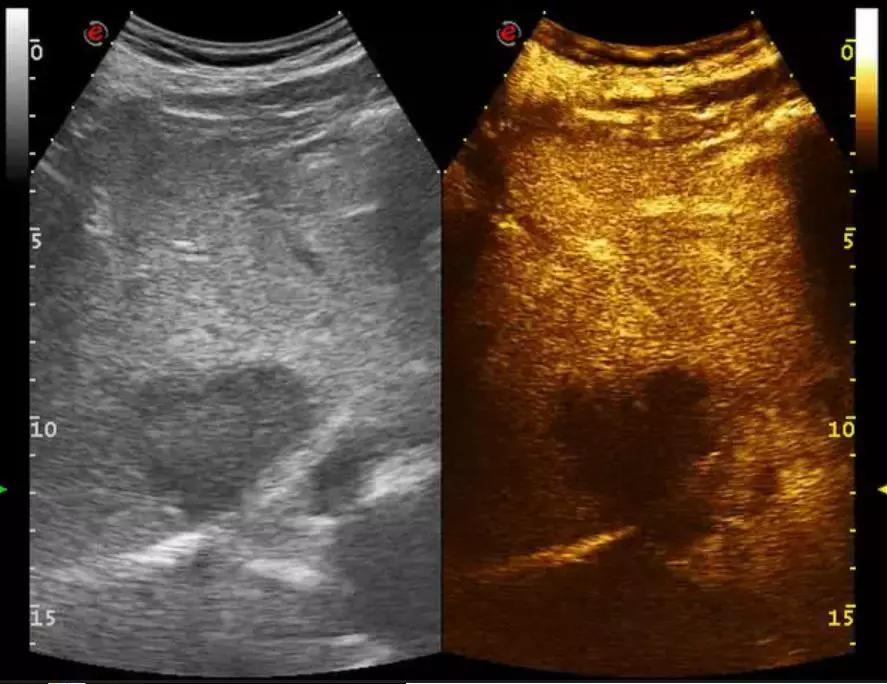

2D:右肝内可见一低回声结节,大小约5.6*4.4*5.7cm。

超声造影:经外周静脉注入声诺维2.4ml,右肝结节动脉期可见稀疏增强,稍高于周边实质回声,门脉期消退,后期消退明显。

超声造影静态图